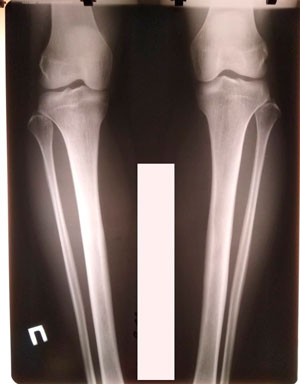

Дата снятия аппаратов - 06.12.2019г.

Срок сращения - 84 дня.